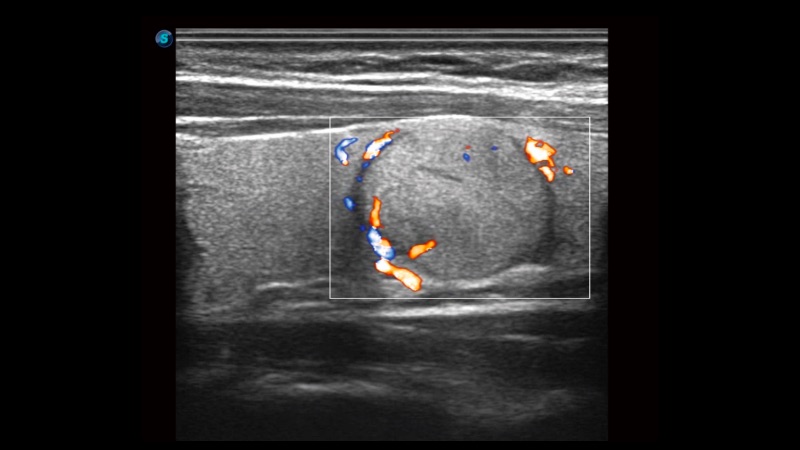

高分辨率血流成像技術(shù)提高了對(duì)低速血流信號(hào)的檢測(cè)能力。在提高空間分辨率的同時(shí),也克服了血流外溢現(xiàn)象,為用戶提供更加真實(shí)的血流動(dòng)力學(xué)信息。

自動(dòng)識(shí)別前后壁內(nèi)膜厚度,為心血管疾病早期評(píng)估提供快速準(zhǔn)確依據(jù)。